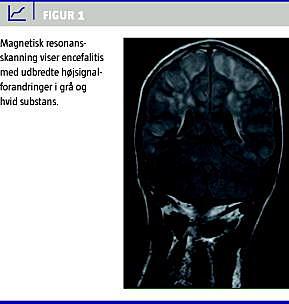

II. En 25-årig mand, der var nyretransplanteret i 2001, blev indlagt akut på mistanke om influenza A (H1N1)v med et døgns anamnese med tiltagende led- og muskelsmerter, febrilia, hovedpine, kvalme og opkastninger. Han var ikke influenzavaccineret. Den vanlige medicin omfattede ciclosporin, mycopheno-latmofetil, prednisolon og alfacalcidol. Ved indlæggelsen var han febril, vågen, klar og orienteret, og havde ikke NRS. Biokemi med C-reaktivt protein < 10, normale leukocytter og trombocytter. Kreatinin var 260 mikromol/l (habituelt niveau på 230 mikromol/l). Røntgen af thorax var normal. Oseltamivir 75 mg daglig påbegyndtes (dosisreduktion svarende til nyrefunktionen). Han klagede over vedvarende hovedpine. I løbet af dagen ændrede han psyke, udviklede cerebral konfusion, blev urolig og rodende. Han havde fortsat ikke NRS, men udviklede et universelt, tonisk krampeanfald, der kuperedes med intravenøst stesolid. CT af cerebrum var upåfaldende. CSV var normal (ingen pleocytose, normalt protein). PCR var negativ for herpes simplex-, varicella zoster- og enterovirus. MR-skanning af cerebrum viste encefalitisforandringer (Figur 1 ) i begge hemisfærer, cerebellum og pons. Der var positiv PCR for influenza A (H1N1)v i næsesvælgpodning, mens den var negativ i CSV. Patienten viste hurtig klinisk fremgang og kunne udskrives i habitualtilstand efter en uges indlæggelse.